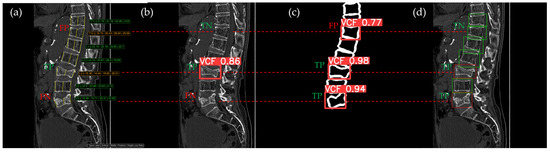

Figure 10, Figure 11, Figure 12, Figure 13 and Figure 14 illustrate typical examples of results for HLR, EEVD, TSVD_SD, and TSVD_DC in patients with acute VCFs. The results of applying different methodologies to the same patient image and identical slice locations were as follows. In the HLR results, each vertebra was marked with yellow solid lines indicating the height measurement lines for the anterior, middle, and posterior regions. The measured height values and HLR percentages were displayed on the right side of the image. If the HLR percentage ranged between 25% and 40%, it was highlighted in orange, while values of 40% or higher were highlighted in red. In the EEVD results, the VCF detection outputs were displayed along with their respective confidence scores based on the input patient images. For the TSVD_SD results, after performing spine segmentation, the model extracted only the spine contour, and the VCF detection results with their corresponding confidence scores were presented. In the TSVD_DC results, bounding boxes were generated for each vertebral body, with normal vertebrae represented in green and vertebrae identified as VCFs displayed in red.

In Figure 11, the acute VCF was also present only at the L2 level, with minimal height loss but evidence of cortical breakage at the anterior upper region. In the HLR method, the result was an FN, while EEVD, TSVD_SD, and TSVD_DC correctly detected it as a TP. In addition, HLR produced FP at the T11 and T12 levels. The T11 vertebra was potentially misinterpreted as a VCF due to its wedge-like deformation; however, the radiological assessment concluded it was normal. Both T11 and T12 were classified as VCFs by HLR based on height measurements exceeding 25% and were classified as moderate VCFs according to the Genant classification.

Figure 11. The VCF detection results from four different methods. (a) HLR, (b) EEVD, (c) TSVD_SD, and (d) TSVD_DC. The acute VCF, as confirmed by the radiologist, was only located at the L2 level. TP, TN, FP, and FN were marked at the same level with a red dotted line. FP occurred at the thoracic vertebrae only with the HLR.